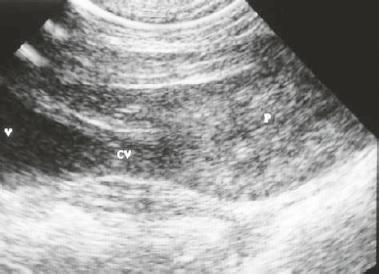

El método más precoz es la ecografía que puede usarse a los 15-18 días de gestación. |

La forma más práctica es la palpación que da excelentes resultados entre 25 y 30 días después del servicio. Es un método seguro, sin problemas ni para la madre ni para los fetos. Debe hacerlo un Veterinario. Además, mediante aparatos especiales, después de los 40 días pueden escucharse los latidos fetales, que se diferencian muy bien de los maternos.